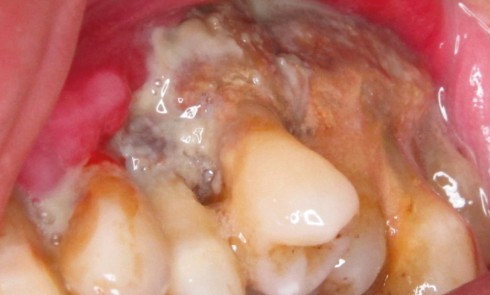

Article réservé à nos abonnés Comment traiter les ostéonécroses des mâchoires ? Traitement médical ou chirurgical ?

En 2014, l’American Association of Oral and Maxillofacial Surgeons (AAOMS) [1] a défini les critères de diagnostic de l’ostéonécrose (tableau 1), les...